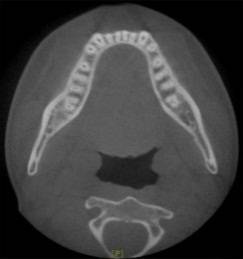

正 畸-正颌联合治疗矫治不对称牙颌面畸形

正畸的基本知识、 特殊情况的正畸、牙套的选择、正畸的关注事项和可能的并发症、正畸-正颌联合治疗、正畸治疗中的常见问题、正畸治疗结束、复发及保持。